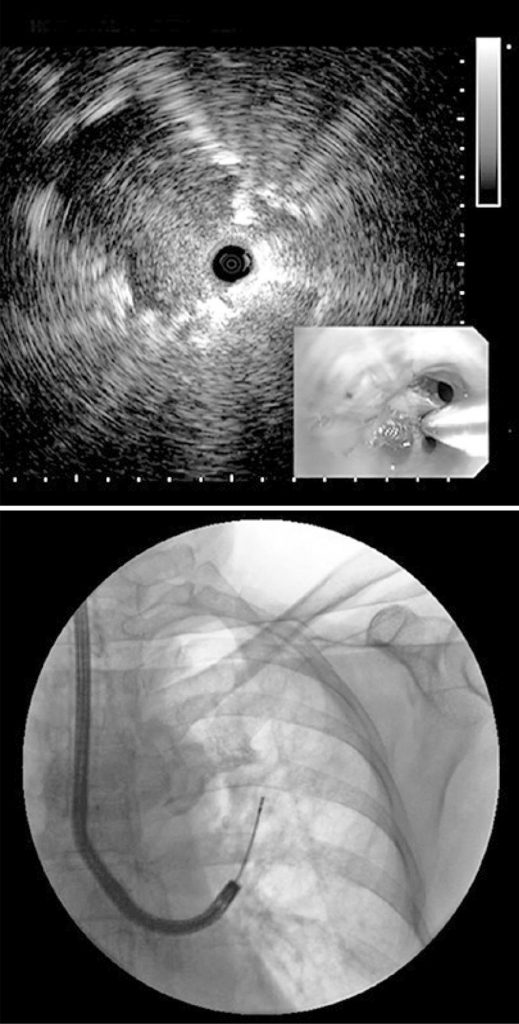

Figura 5

Ultrassonografia endobrônquica radial e biópsia transbrônquca guiada por fluroscopia